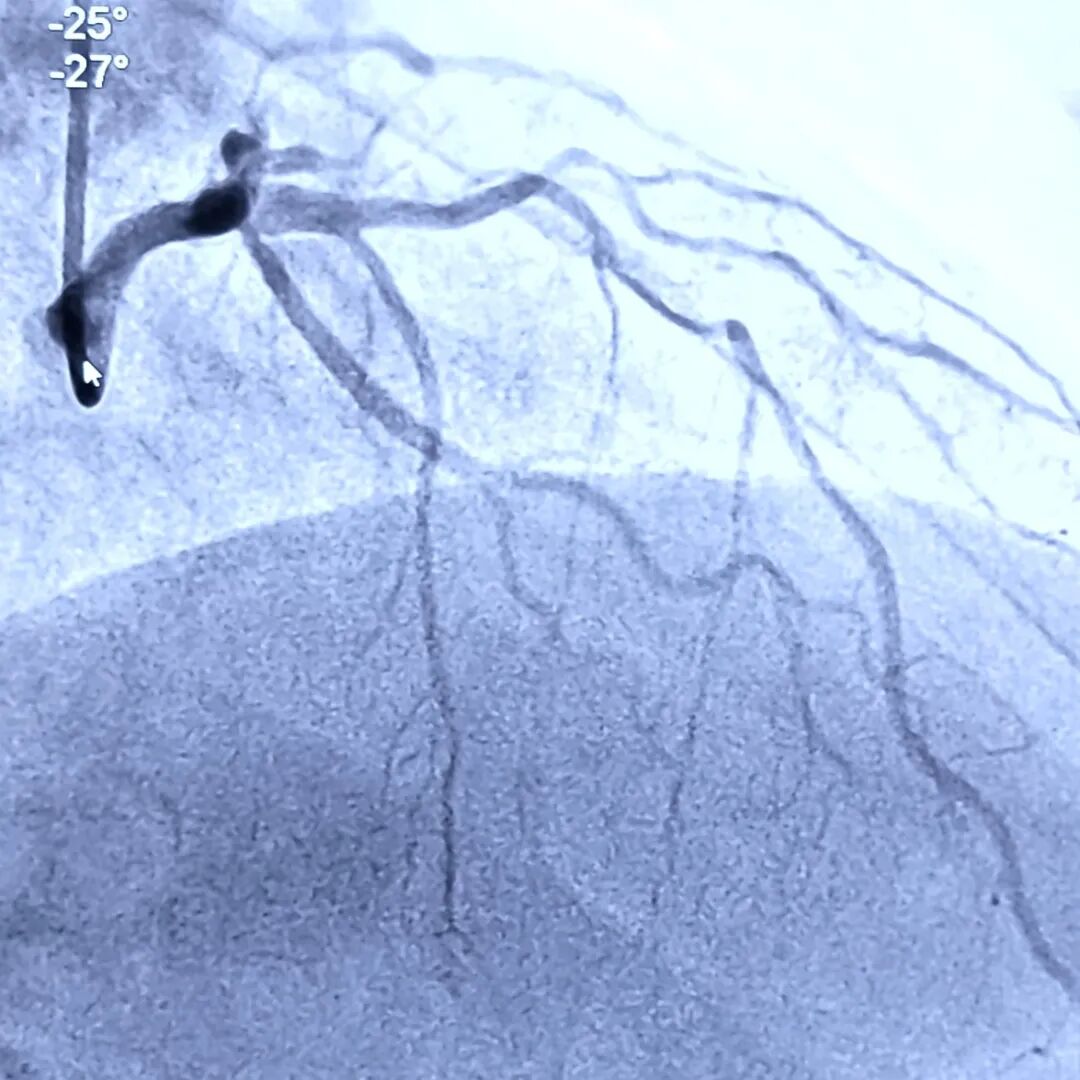

能不能实际应用?用一个前降支与间隔支的分叉(图20)来配准试试。

图20、选取了前降支与第一间隔支来配准。造影图上间隔支在下方,那我们最后配准的IVUS图间隔支开口应该在屏幕的下方,而且靠近嵴部的地方略有点往左斜。

右头位能够看到导丝与换能器分开,导丝在下方,从左往右走(图21)。右头位探测器在右侧。这样就完成了前面三步。第四步要打开此处的IVUS,是否在导丝的下方,如果不是,通过旋转来进行配准对齐。